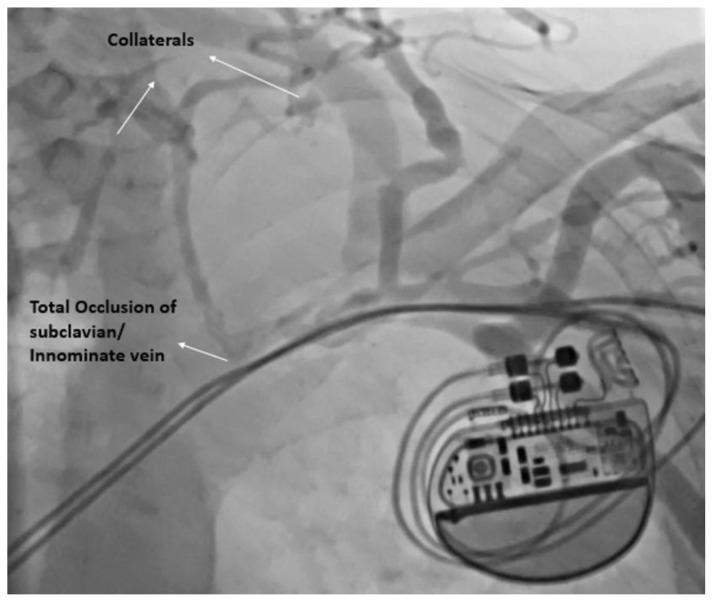

Methods: This study was a single-center prospective, observational study. Demographic, clinical, procedural, and device data was collected. All patients underwent a preimplant contrast and repeated venography at twelve months to look for upper limb venous anatomy, obstruction, or collaterals.

Abstract Image